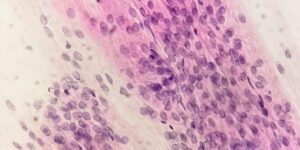

Trichomoniasis, a.k.a. “trich,” is a common, treatable sexually transmitted disease caused by Trichomonas vaginalis (a causative parasite).